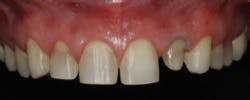

Margin placement should be based on restoration type, periodontal health and characterization, and esthetics. Subgingival margins continue to be the most frequent technique for impressions for fixed restorations, although in many cases they can be avoided. Improved ceramics and color matching, in addition to excellent adhesive cements, allow for margin placement that is equigingival and often supragingival. Many veneers can now be prepared and placed with an equigingival or supragingival margin, often using no or only one cord (Fig. 6).

Fig. 6 — Veneer preparations using one cord (two were used for the lateral crown).